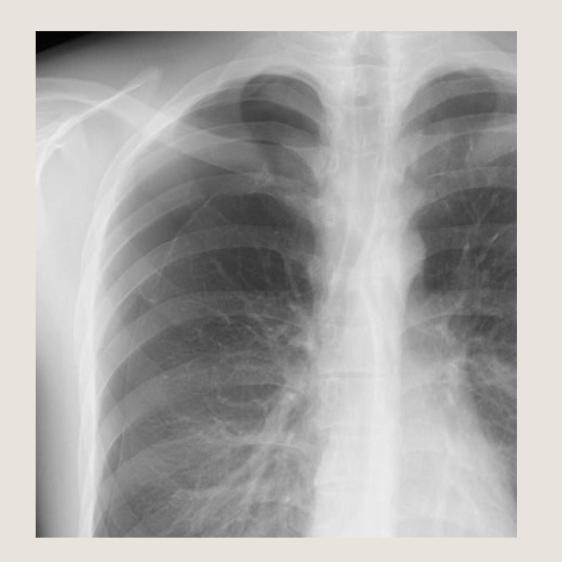

気胸の胸部レントゲン画像

気胸の胸部レントゲン画像を見てみましょう。肺に穴が開いて、肺がしぼんでしまうのが気胸ですが、肺の上の方がしぼむ事が多いです。なので、「どこに気胸があるでしょうか?」などと聞かれた場合は、肺の上の方を重点的に見るといいです。

どうでしょうか? 右肺の上の方に、なんだか「線」が見えるでしょう?